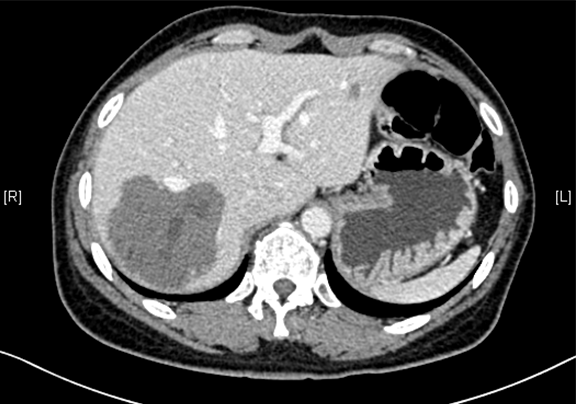

术前CT检查:动脉期

静脉期

平衡期